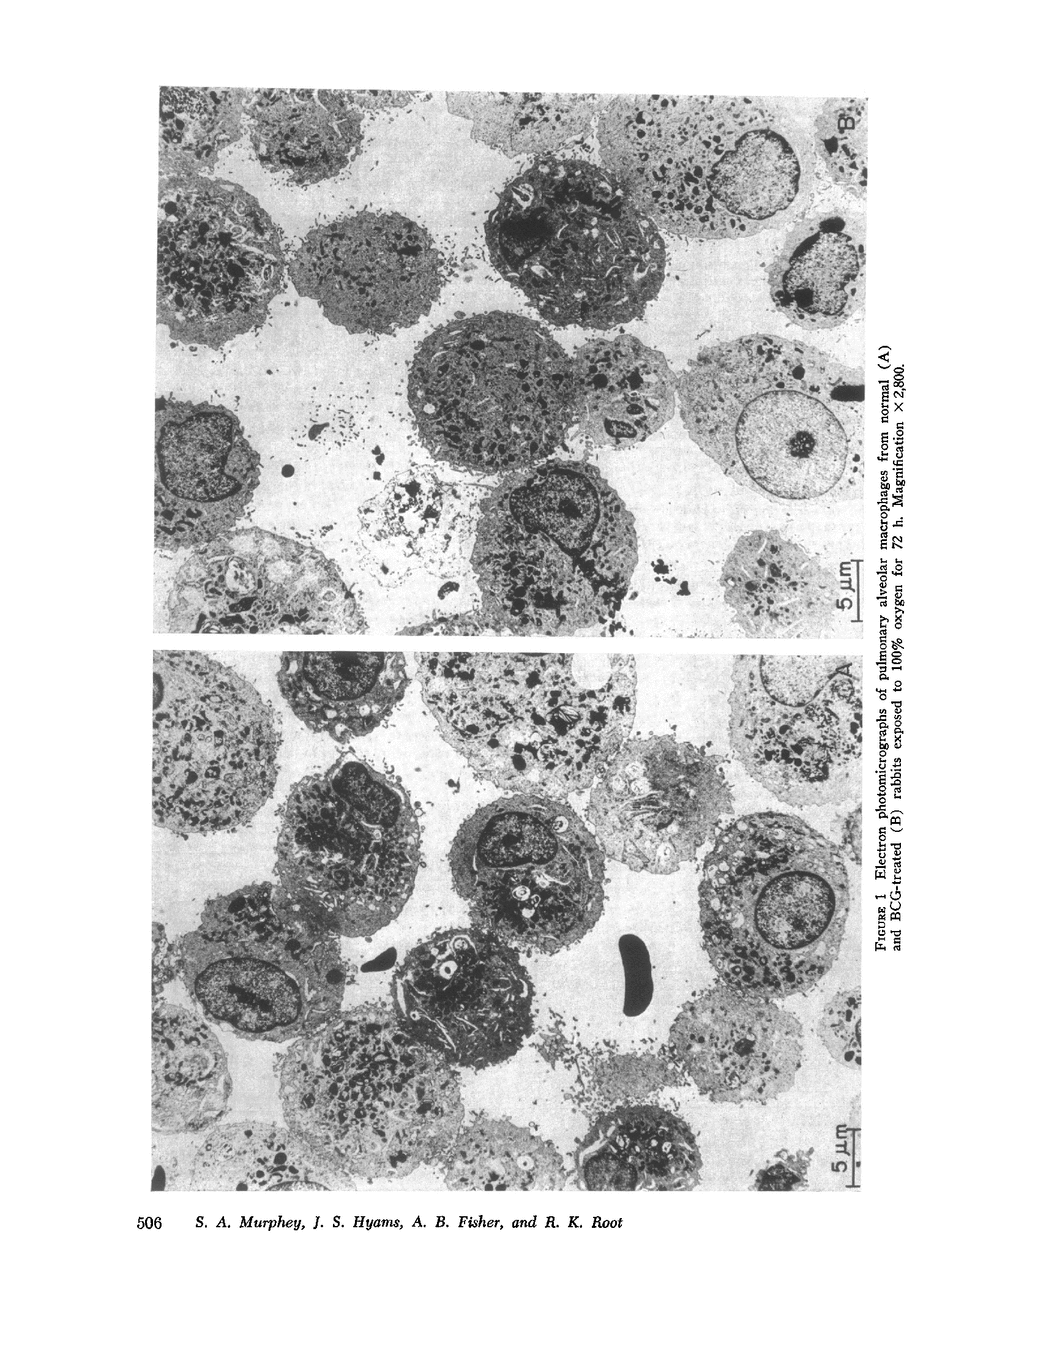

Bacterial infection may complicate pulmonary oxygen (O2) toxicity, and animals exposed to high O2 concentrations show depressed in vivo pulmonary bacterial inactivation. Therefore, in vitro studies were undertaken to define the mechanism by which O2 alters pulmonary antibacterial activity. Normal and BCG pretreated rabbits were exposed to 100% O2 for 24, 48, and 72-h periods. Pulmonary alveolar macrophages (PAM) were obtained from the experimental animals and from nonoxygen exposed controls by bronchopulmonary lavage. O2 exposure did not alter cell yield or morphology. PAMs were suspended in 10% serum-buffer, and phagocytosis of (14C)Staphylococcus aureus 502A and (14C)Pseudomonas aeruginosa was measured. Comparison of the precent uptake of the 14C-labeled S. aureus after a 60-min incubation period demonstrated that normal PAMs exposed to O2 for 48 h showed a statistically significant increase in phagocytosis when compared to their controls (43.5 vs. 29.2%). A similar, but smaller increase was seen after 24-h O2 exposures. 48 and 72-h O2 exposures produced no significant changes in phagocytosis in PAMs from BCG-stimulated rabbits. Normal PAMs also showed an increased phagocytosis of Ps. aeruginosa after 48-h oxygen exposure. No impairment of in vitro bactericidal activity against either S. aureus 502A or Ps. aeruginosa could be demonstrated in PAMs from normal rabbits exposed to O2 for 48 h. These results indicate that the in vitrophagocytic and bactericidal capacity of the rabbit PAM is relatively resistant to the toxic effects of oxygen, and that imparied in vivo activity may possibly be mediated by effects other than irreversible metabolic damage to these cells. The mechanism for the observed stimulation of phagocytosis remains to be determined.